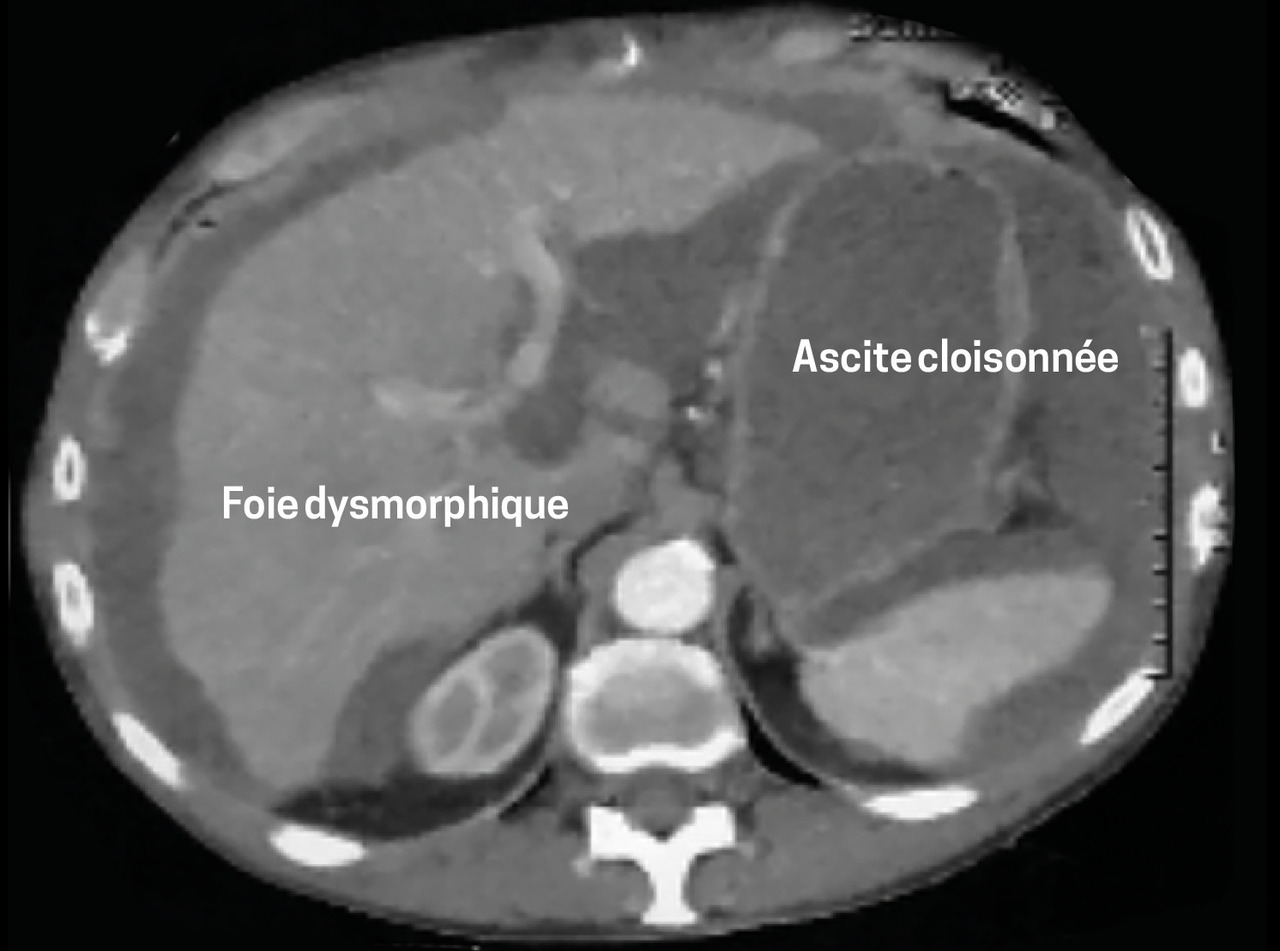

Le scanner abdominal (fig. 1 et 2)montre un volumineux épanchement ascitique diffus, un foie dysmorphique. Le bilan d’hépatopathie est négatif. L’ACE est élevé (8,79 µg/L), comme le CA 19,9 (57 UI/mL).

L’échographie révèle une ascite multi-cloisonnée. La ponction retrouve un liquide gélatineux ; l’analyse anatomopathologique est en faveur d’une maladie gélatineuse du péritoine.

La tomodensitométrie et l’échographie apportent des signes radiologiques complémentaires : respectivement encoches hépatiques et images de cloisons.